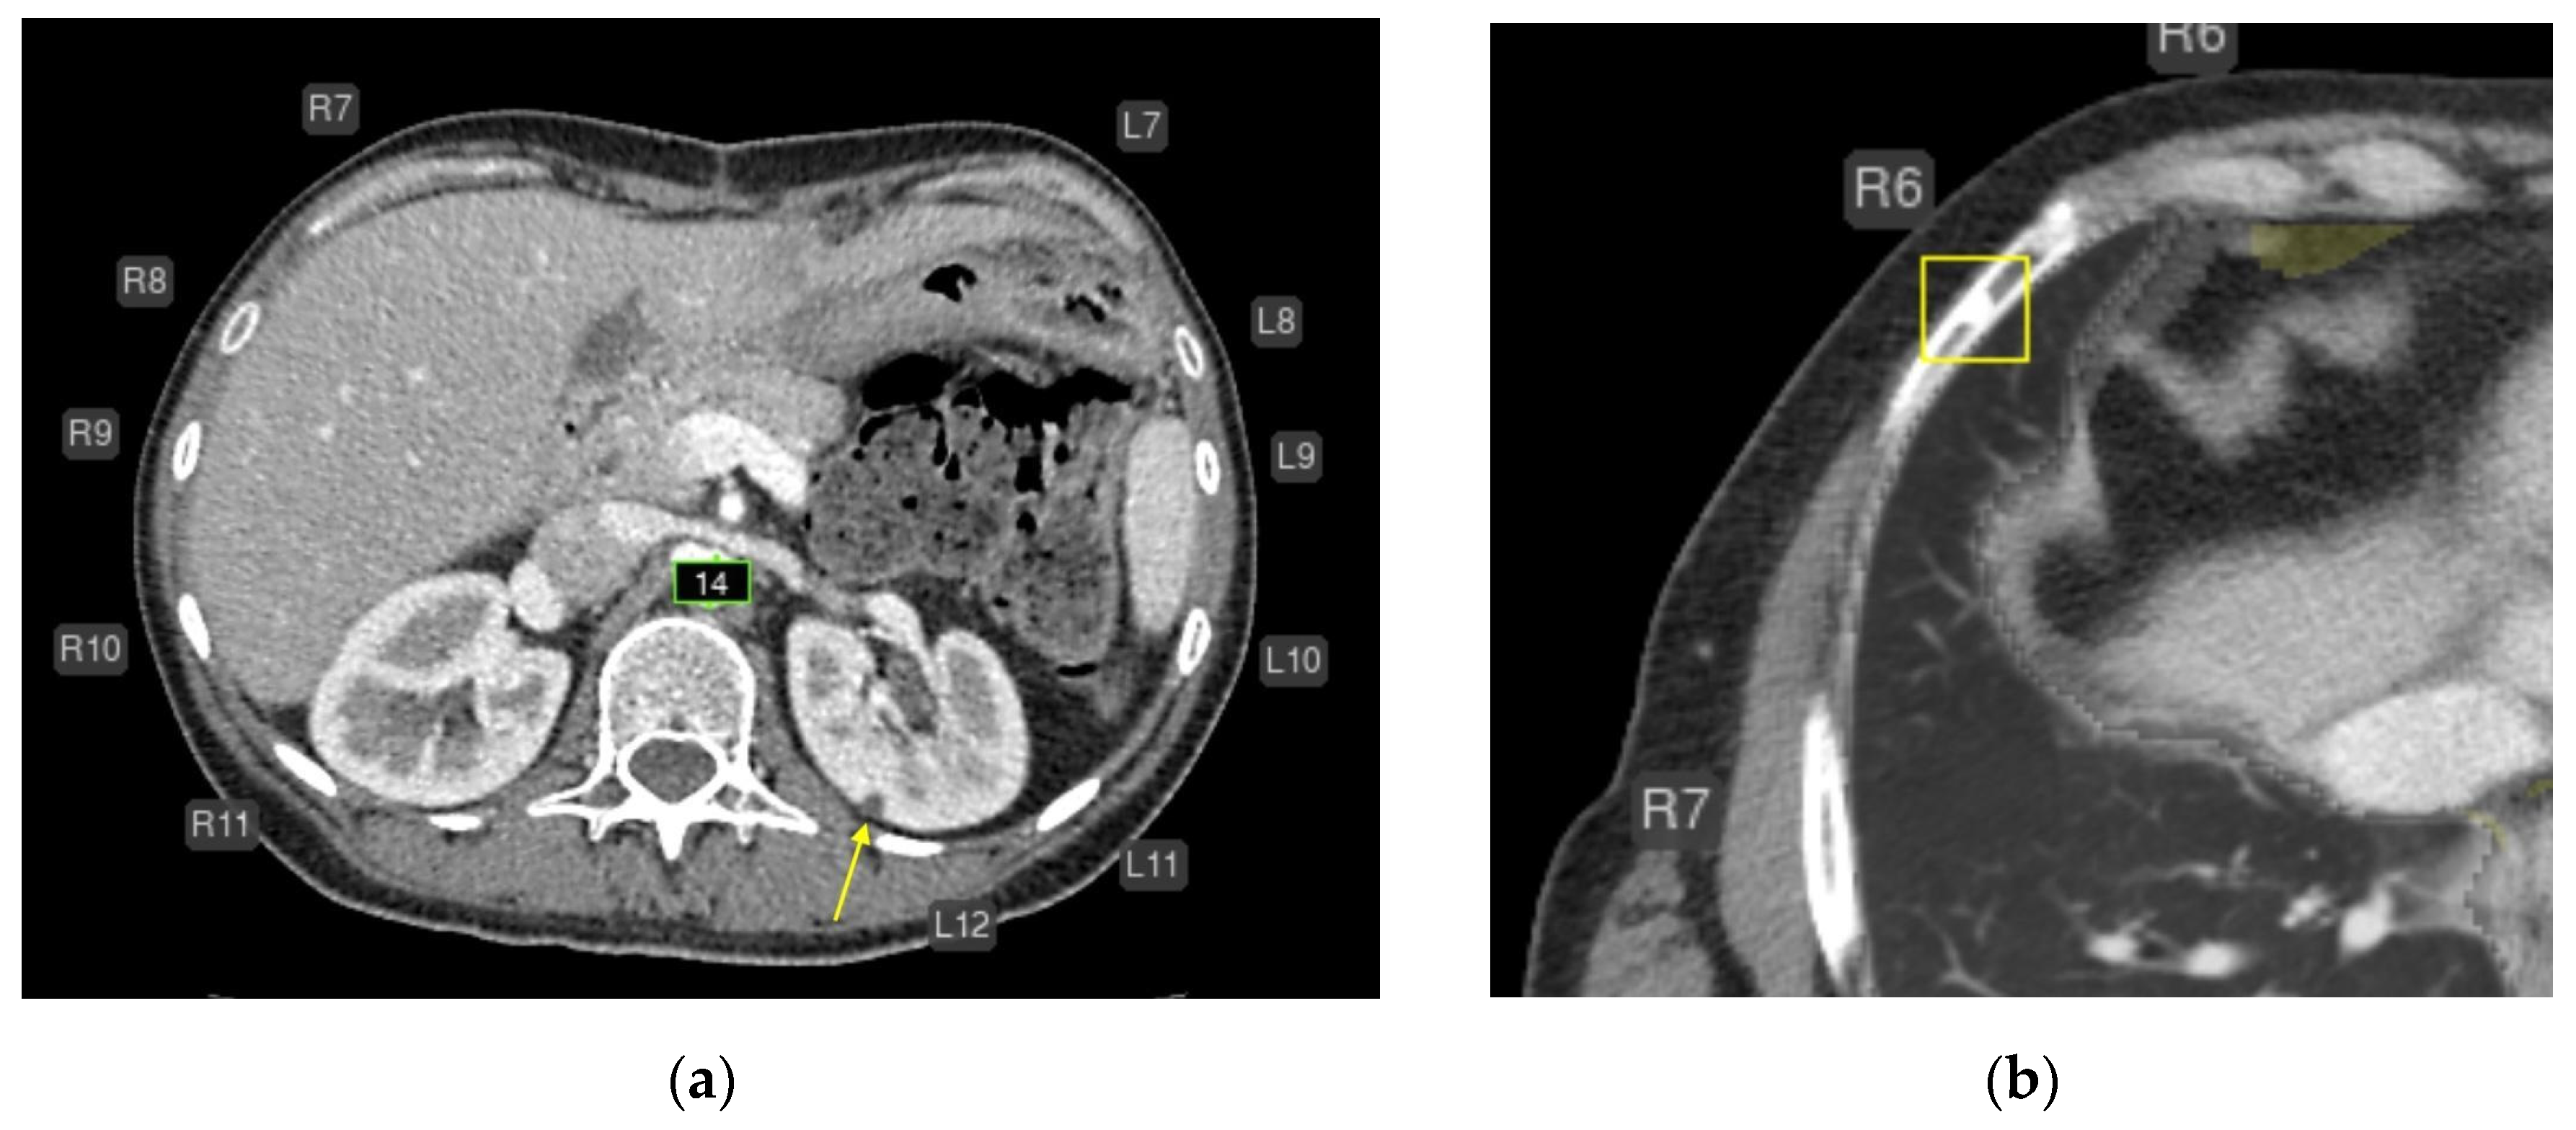

- Intrathoracic lymph nodes (16);

- Pulmonary nodules (15);

- Impaired aeration (15);

- Aortic dilatation/aneurysm (10);

- Adrenal thickening (10) (Figure 5).